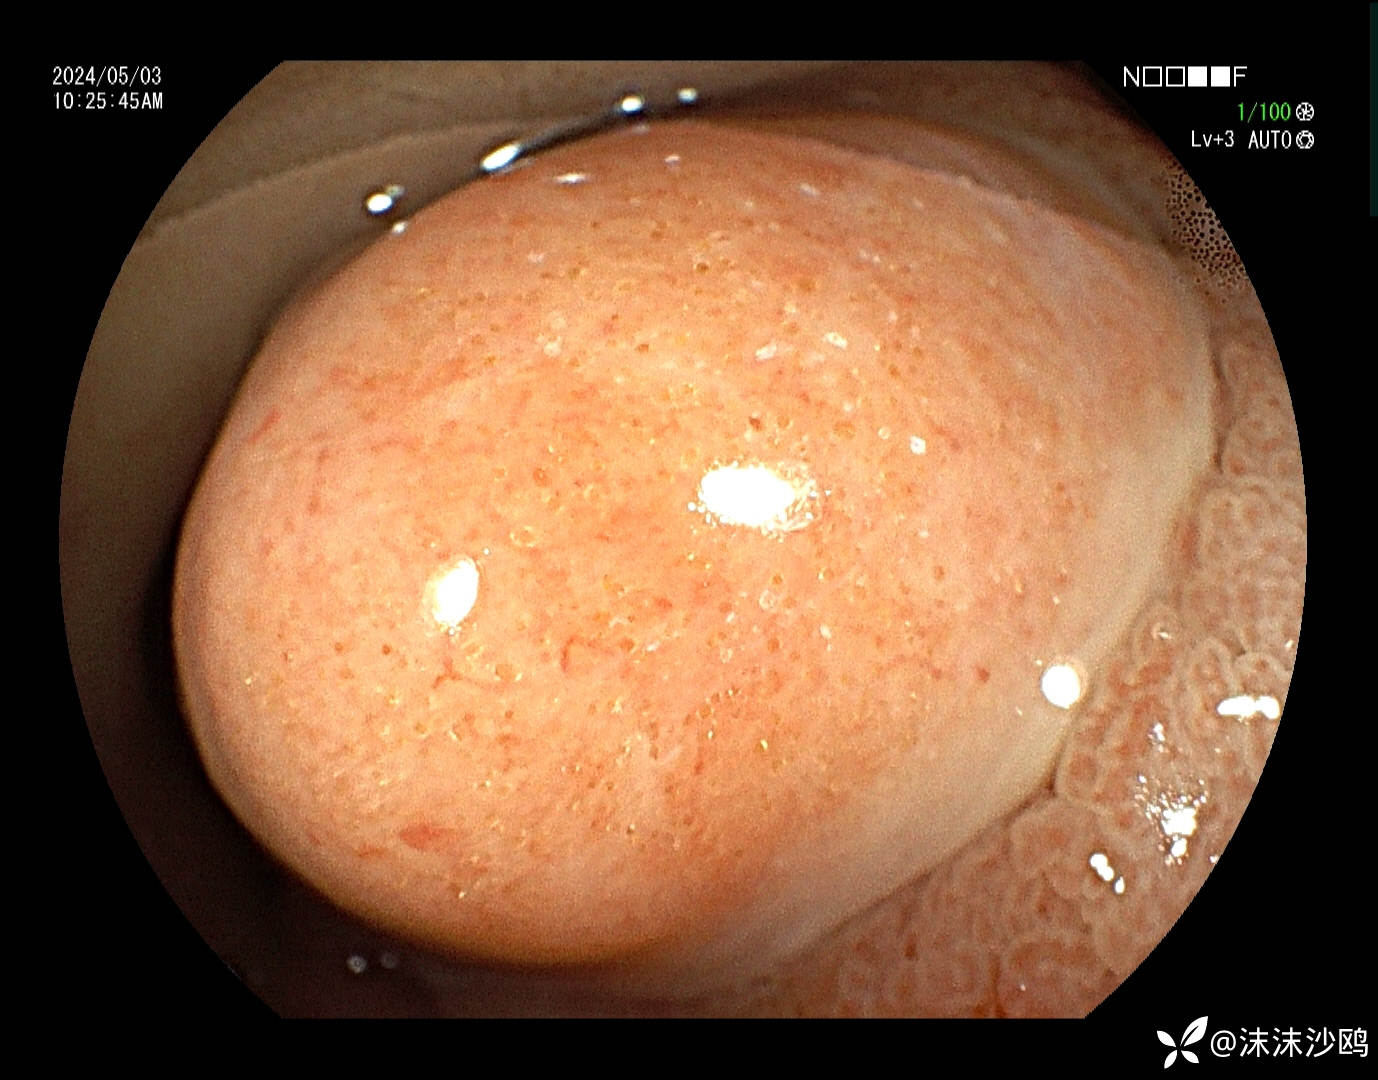

表面没有明显的腺管结构,覆较多黏液冲洗不掉

BLI